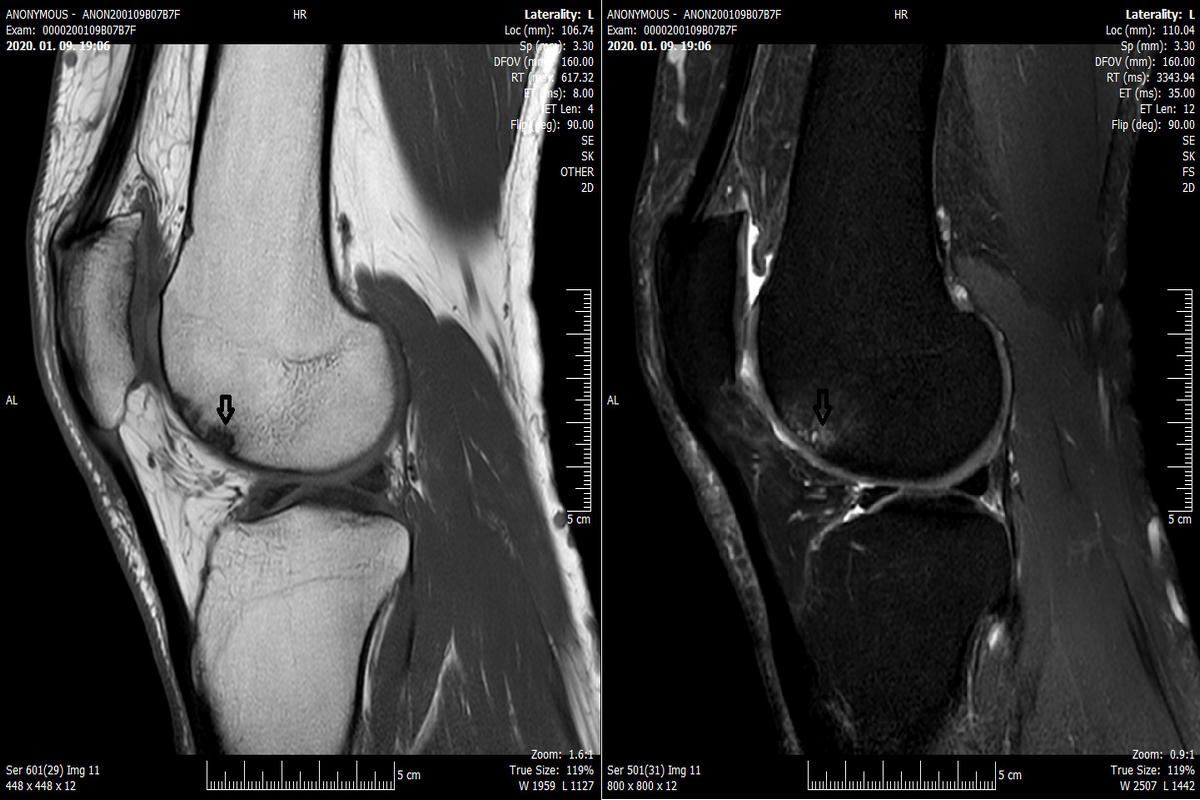

Η διάγνωση βασίζεται αρχικά στην κλινική εξέταση, με εκτίμηση της κινητικότητας, της ευαισθησίας και της σταθερότητας του γόνατος. Ο απεικονιστικός έλεγχος παίζει καθοριστικό ρόλο, με τη μαγνητική τομογραφία (MRI) να αποτελεί τη μέθοδο εκλογής, καθώς απεικονίζει με ακρίβεια το μέγεθος, το βάθος και την εντόπιση της βλάβης.

Σε επιλεγμένες περιπτώσεις, η διαγνωστική αρθροσκόπηση προσφέρει άμεση και αξιόπιστη εκτίμηση της κατάστασης του αρθρικού χόνδρου.